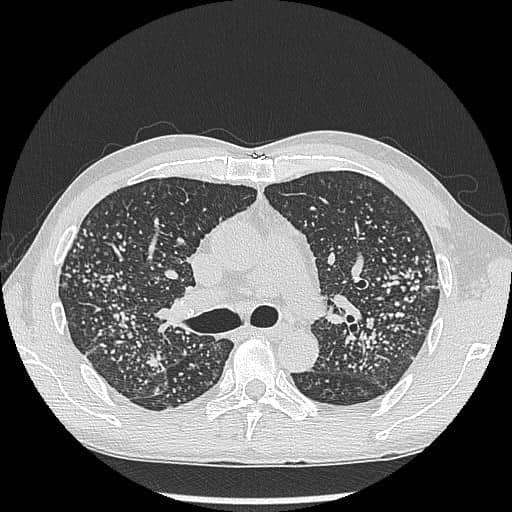

該男子長滿肺結節

▲照X光發現,該男子長滿肺結節,如“滿天星”。(圖片來源:“胸腔內科醫生蘇一峰”facebook專頁)